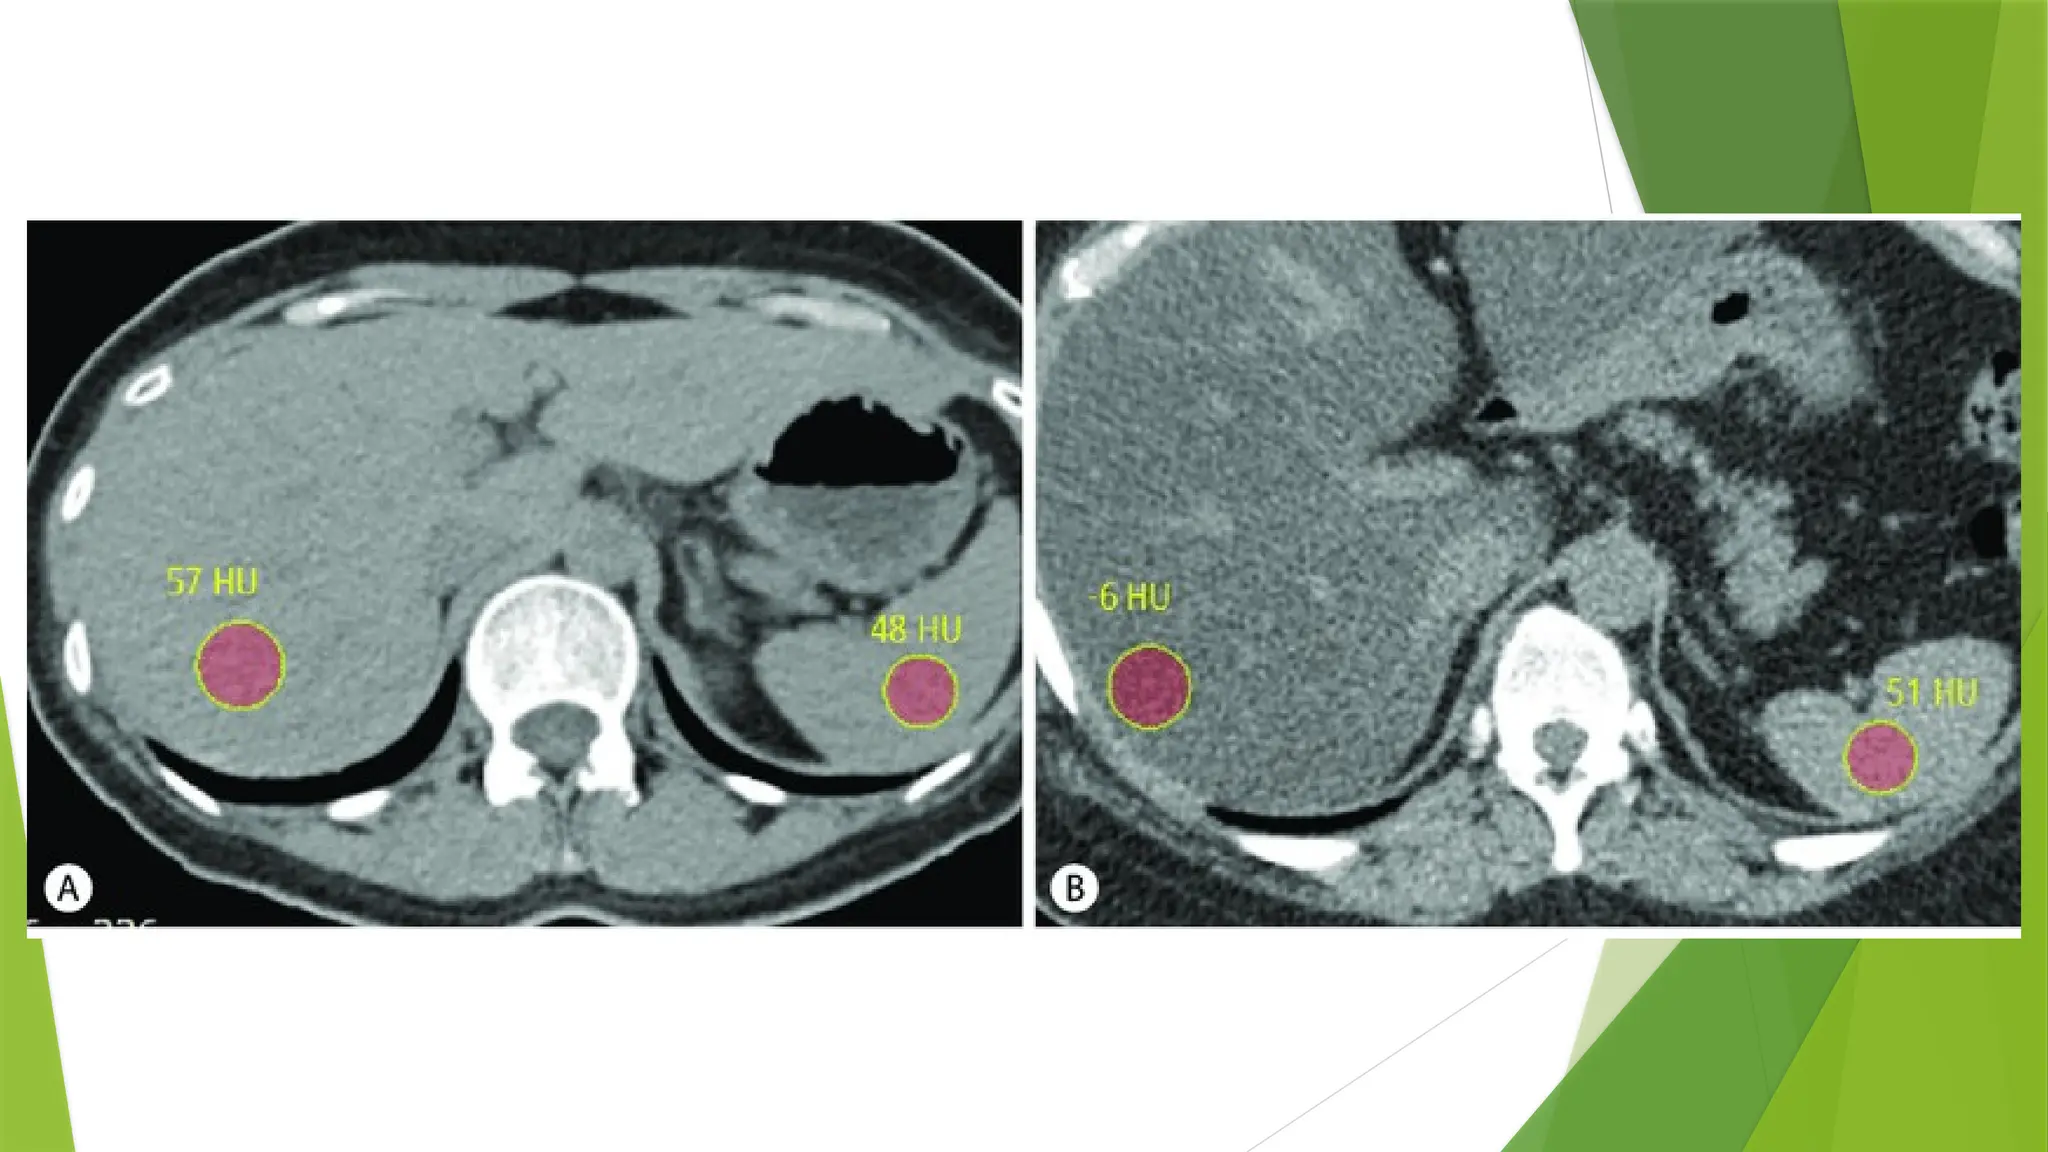

Basics And Principles Of Ct Scan And Windowing Pptx The computer system performs image manipulation and various image processing operations such as windowing, image enhancement, image enlargement and measurements, multiplanarreconstruction, three dimensional (3d) imaging, an quantitative measurements. Computed tomography basic principles introduction computed tomography (ct) is a medical imaging method employing tomography. the word "tomography" is derived from the greek tomos (slice) and graphein (to write). Ct produces a volume of data which can be manipulated, through a process known as windowing, in order to demonstrate various structures based on their ability to block the xray beam. Sir godfrey newbold hounsfield cbe (28 august 1919 – 12 august 2004) was an english electrical engineer who shared the 1979 nobel prize for physiology or medicine with allan mcleod cormack for his part in developing the diagnostic technique of x ray computed tomography (ct). • the creation of these shades of gray is based on basic radiation principles. • the degree to which an x ray beam is reduced by an object is referred to asattenuation. The document discusses the history, components, principles, types (including spiral, multidetector, angiography), advantages, and risks of ct scanning. ct guided procedures such as biopsy and drainage are also summarized. download as a pptx, pdf or view online for free.